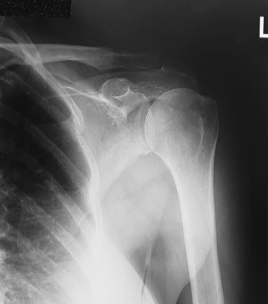

is this a normal or dislocated shoulder? how do you know?

normal, head of humerus superimposed over base of Y